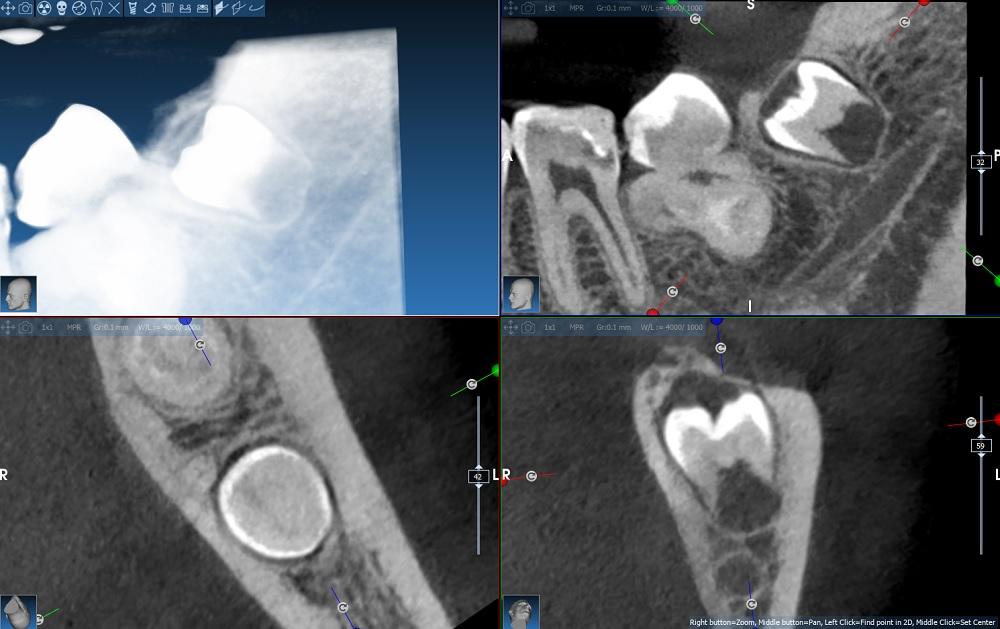

- Uzębienie stałe. Brak zębów: 48. Związany z zębem 37 układ radiologicznych zacienień o wysyceniu zbliżonym do zębiny i szkliwa oraz przejaśnień mogących odpowiadać układowi kanałów korzeniowych, co najpewniej odpowiada zębowi wgłobionemu, do różnicowania ze zmianami hamartomatycznymi, w tym przede wszystkim zębiakiem złożonym – do dalszej diagnostyki klinicznej. Zawiązek zęba 18 zatrzymany w pozycji zbliżonej do pionowej. Zawiązek zęba 38 zatrzymany mezjalnokątowo. Przechylenie zębów 11, 21. Stłoczenie zębów dolnego łuku. (5-8)